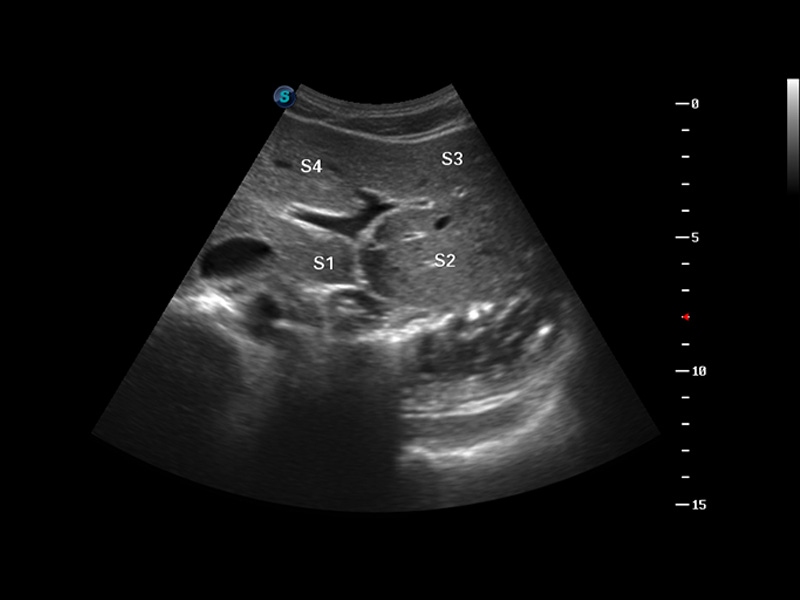

成像技术

多波束形成器

μ-Scan微米成像

谐波成像

实时宽景成像

空间复合成像

3D/4D成像